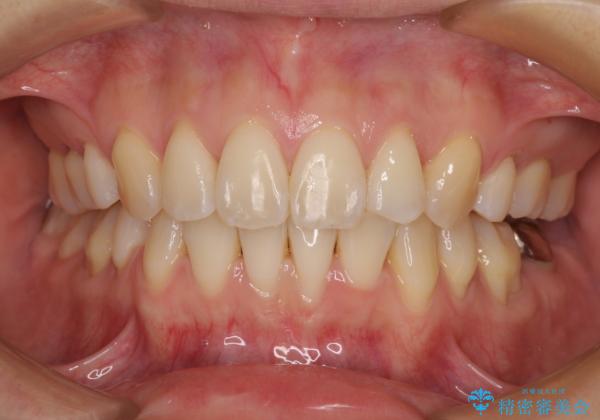

前歯のデコボコを抜歯矯正で改善 メタル装置で費用を抑える

- 前歯のデコボコと口元の突出感を気にして来院された患者様です。

非抜歯矯正ではデコボコを解消することでより口元が突出してしまうため、上下左右の小臼歯4本の抜歯を行い、ワイヤー装置による矯正治療を行うこととしました。

もう少し口元の突出感を改善したかったのですが、舌の突出癖が影響し下顎前歯が唇側に押させる仕上がりとなりました。